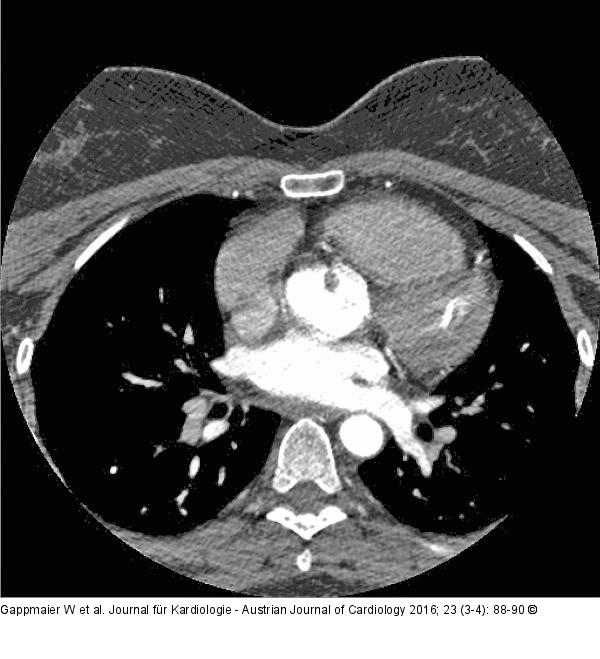

Abbildung 2: CT-Angiographie CT-Angiographie: Befund einer verdächtigen kleinen Kontrastmittelaussparung im Bereich der Aortenklappe |

Abbildung 2: CT-Angiographie

CT-Angiographie: Befund einer verdächtigen kleinen Kontrastmittelaussparung im Bereich der Aortenklappe |